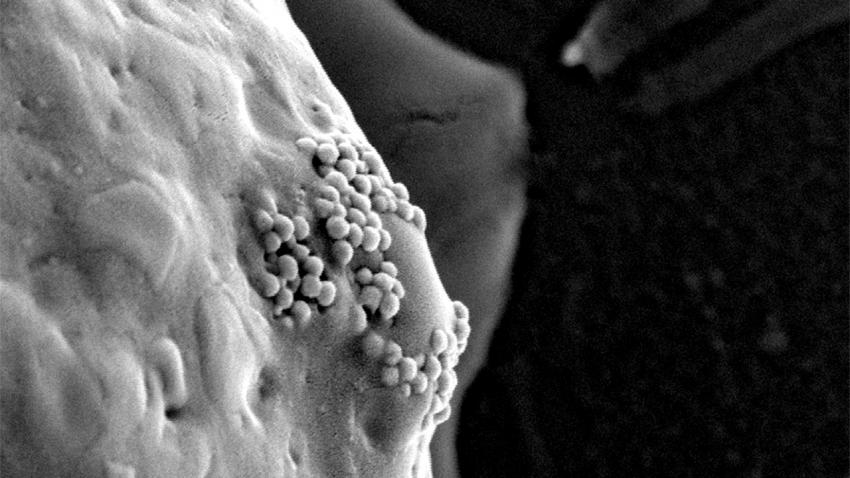

Những cụm hạt vàng dưới kích thước nano đang bị tế bào ung thư nuốt vào bên trong.

Trong quá tŕnh phát triển và bành trướng, các tế bào ung thư sẽ bao bọc và nuốt chửng các hạt nano vàng này vào bên trong. Sau đó, các nhà khoa học sẽ chiếu sáng các hạt nano vàng bằng tia laser hồng ngoại, các hạt này sẽ nóng lên với nhiệt độ cao và tiêu diệt các tế bào ung thư.